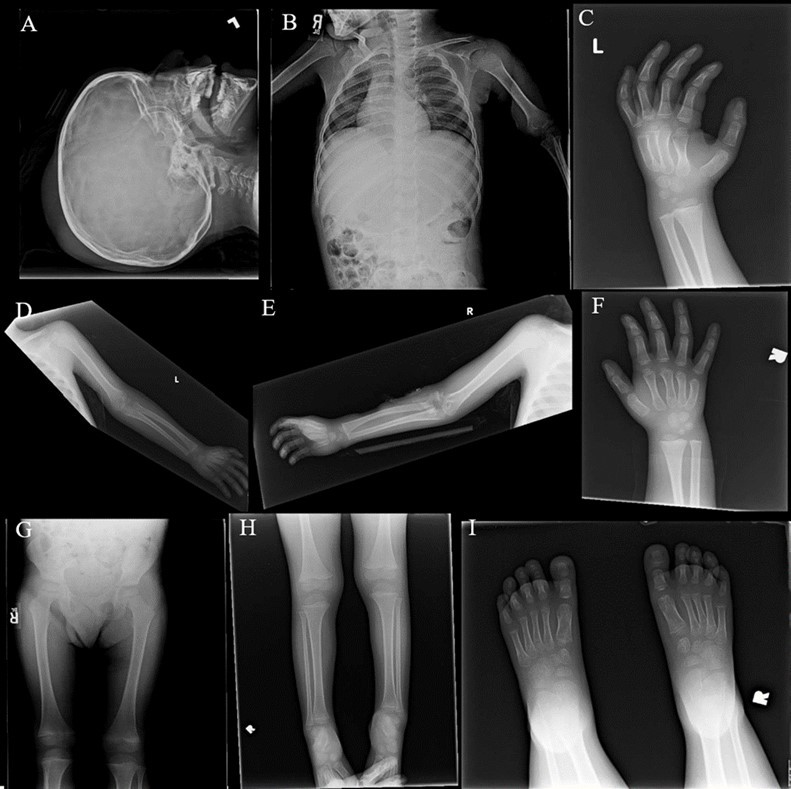

From a musculoskeletal standpoint, MRIs of the cervical, thoracic, and lumbar spine were within normal limits. The patient was started on scheduled acetaminophen for pain management. A CT of the head without contrast showed right high convexity scalp soft tissue swelling without acute intracranial abnormality (Figure 1A – 1F). A complete bone survey was negative for sources of trauma (Figure 2B – 2I) but did note calvarial soft tissue edema (Figure 2A). A head ultrasound confirmed the fluctuance on the patient’s skull to be a subgaleal hemorrhage (Figure 3A – 3C) of 9 mm thickness at its greatest.

Figure 2A - 2J.X-Ray complete bone survey. 2A: Lateral view of the skull, 2V. 2B: Frontal view of chest, abdomen and pelvis (spine), 1V. 2C: Frontal view of left humerus, 2V. 2D: Frontal view of left hand, 2V. 2E: Frontal view of right humerus, 2V. 2F: Frontal view of right hand, 2V. 2G: Frontal view of both femora, 1V. 2H: Frontal views of both lower legs, 2V. 2I: Frontal views of both feet, 2V. Findings include calvarial soft tissue edema. No additional injury detected on these radiographs.